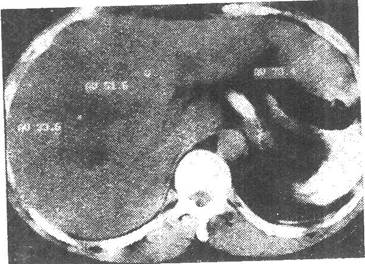

患者男性,49岁,发现乙肝十余年,反复腹痛,腹胀黄疸月余,CT图像如下,最有可能的诊断是( )。

CT平扫 动脉期增强

[单选题]患者男性,49岁,发现乙肝十余年,反复腹痛,腹胀黄疸月余,CT图像如下,最有可能的诊断是( )。CT平扫动脉期增强门静脉期增强A.肝肉瘤B.肝血管瘤

[单选题]患者男性,49岁,发现乙肝十余年,反复腹痛,腹胀黄疸月余,CT图像如下,最有可能的诊断是( )。CT平扫动脉期增强门静脉期增强A.肝肉瘤B.肝血管瘤

[单选题]患者男,49岁。发现乙肝十余年,反复腹痛,腹胀黄疸1个月余,CT图像如下,最有可能的诊断是A.肝血管瘤B.肝再生结节C.肝癌D.肝肉瘤E.肝腺瘤

[单选题,A2型题,A1/A2型题] 患者男性,49岁,发现乙肝十余年,反复腹痛,腹胀黄疸月余,CT图像如下,最有可能的诊断是()。A . 肝肉瘤B . 肝血管瘤C . 肝癌D . 肝再生结节E . 肝腺瘤

[单选题]患者男性,49岁,发现乙肝十余年,反复腹痛,腹胀黄疸月余,CT图像如下,最有可能的诊断是( )。A.肝肉瘤B.肝血管瘤C.肝癌D.肝再生结节E.肝腺瘤

[单选题]患者男性,49岁,发现乙肝十余年,反复腹痛,腹胀黄疸1个月余,CT图像如下,最有可能的诊断是()A.肝血管瘤B.肝再生结节C.肝癌D.肝肉瘤E.肝腺瘤

[单选题]患者男性,49岁,发现乙肝十余年,反复腹痛,腹胀黄疸1个月余,CT图像如下,最有可能的诊断是()。A . 肝血管瘤B . 肝再生结节C . 肝癌D . 肝肉瘤E . 肝腺瘤